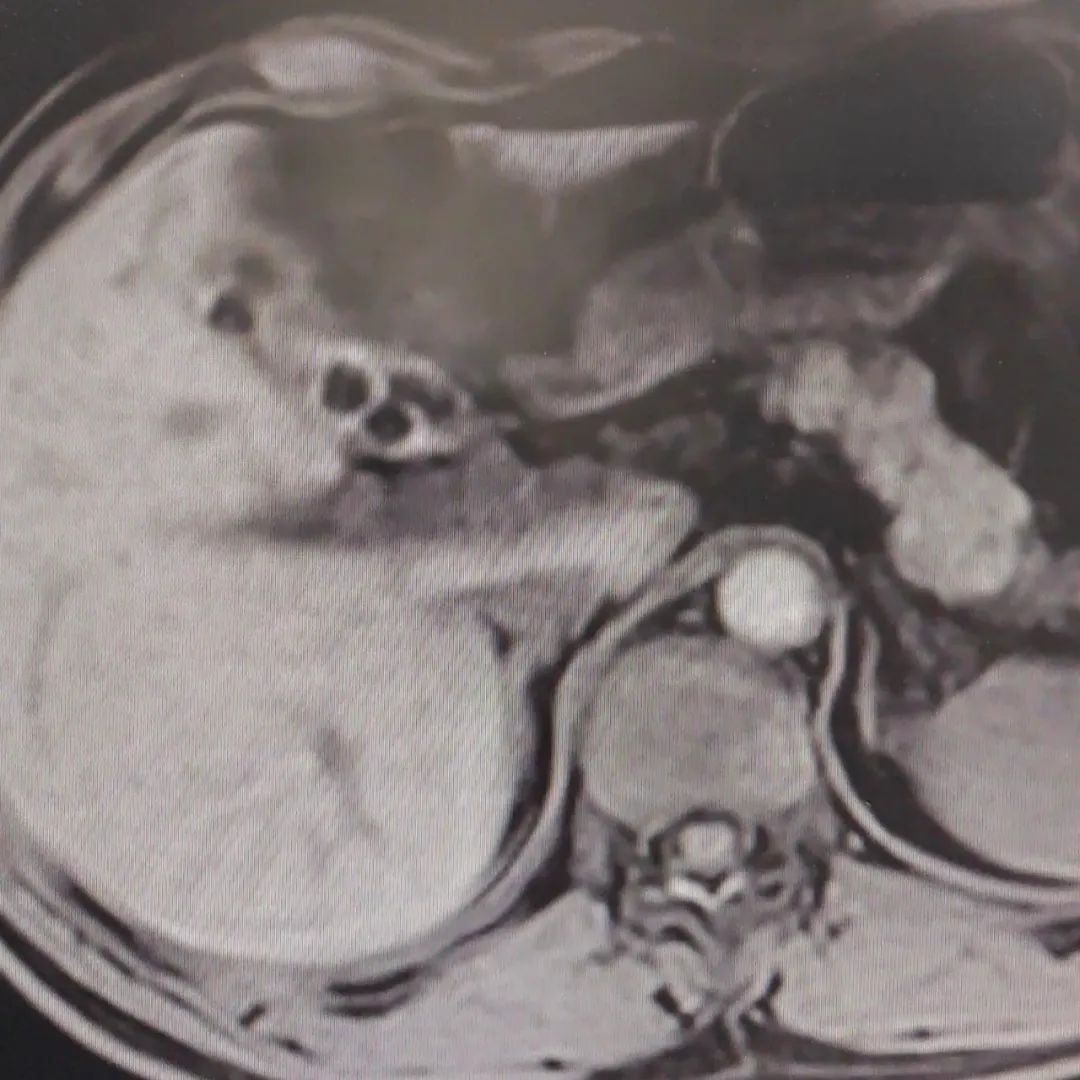

在当地医院检查后,小薇确诊胆囊充满型结石。影像可见,她的胆囊里密密麻麻地长满了结石,数量有上百颗。